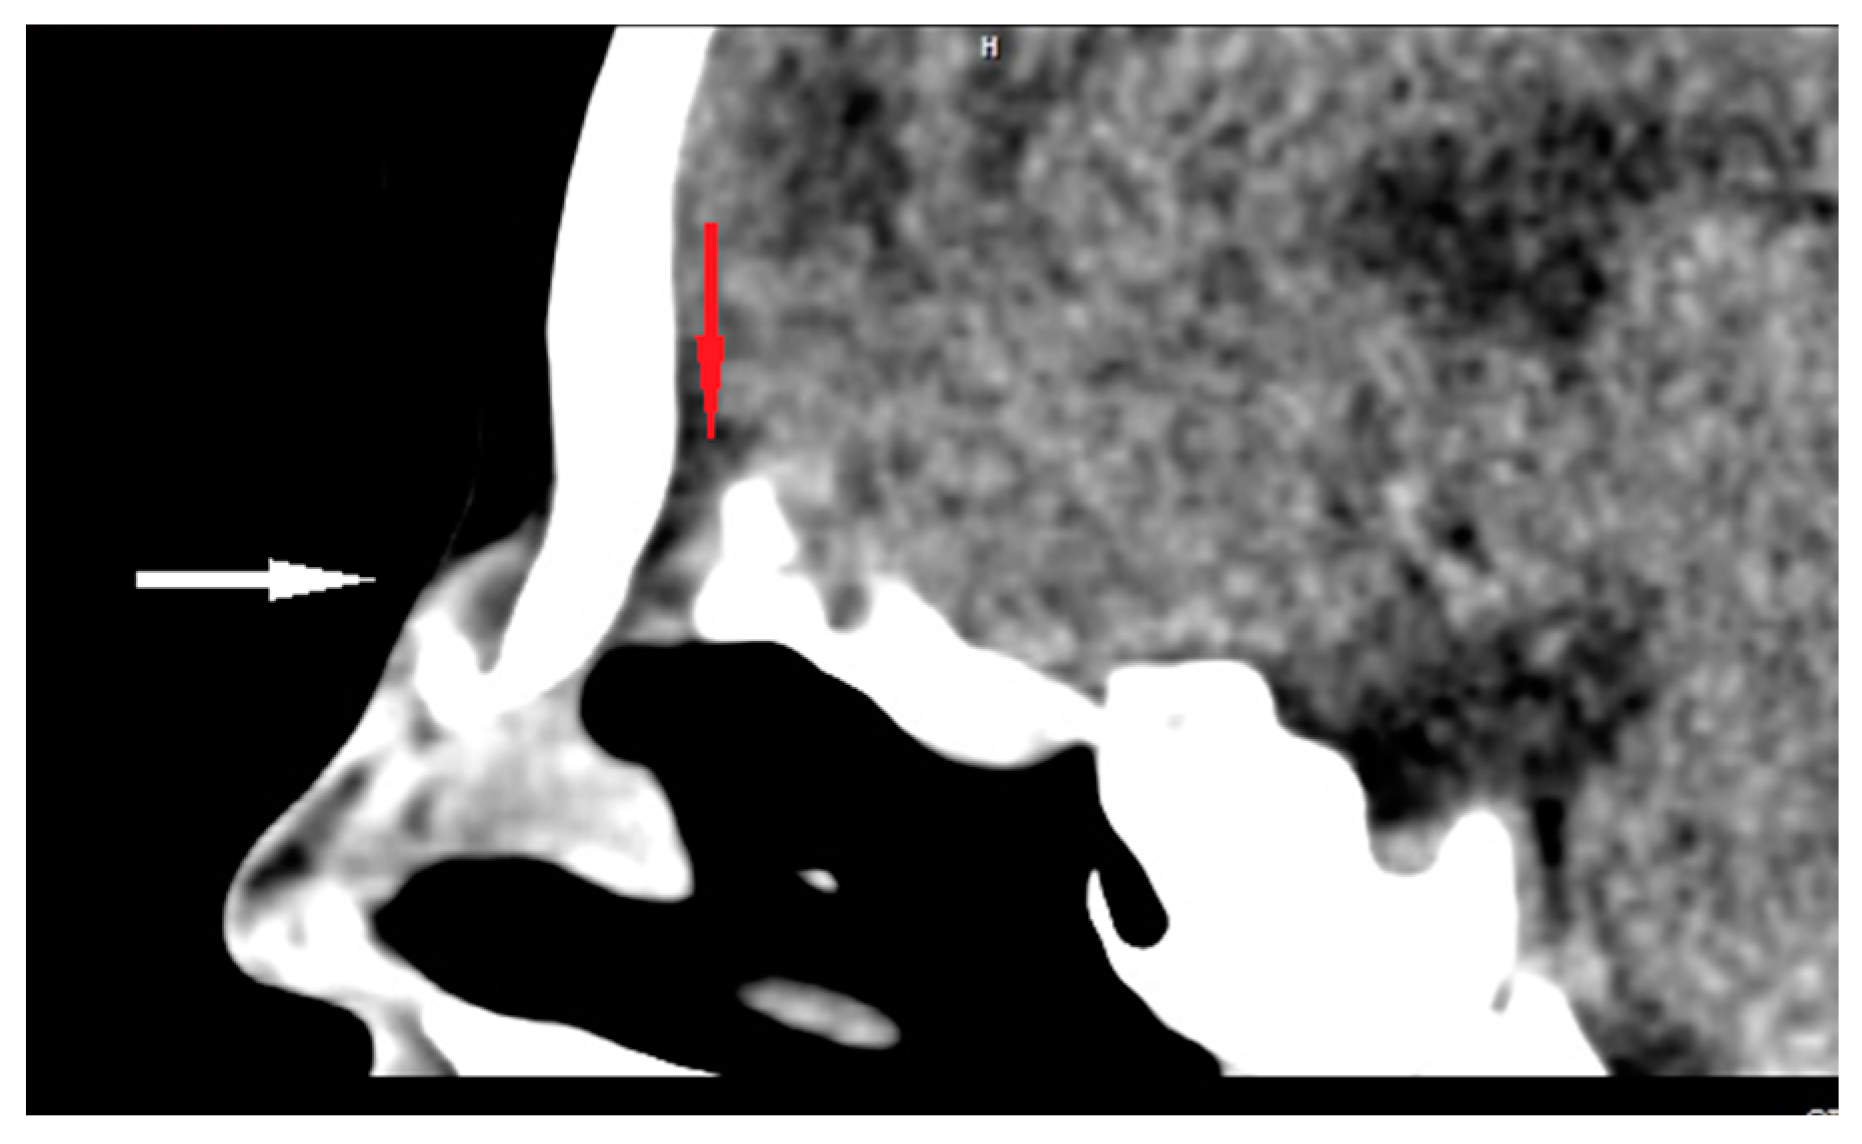

| Radiological characteristics | CT | No correlation between the particular location of the sinus ostium or cyst and the presence of intracranial extension; bifid crista galli and widening of foramen caecum (suggestive of intracranial extension); dermoid cyst—density of fat; epidermoid cyst—density of water | Bony defect may be revelaed | Developmental bony defect of the skull base |

| MRI | Variable signal intensity depending on the protein content; fat-suppressed T1-weighted images—differentiation between skull base defects and enhancing non-ossified cartilage of anterior cranial fossa; DWI—typically high-signal-intensity lesion with corresponding low signal intensity on ADC maps | Discontinuity with the brain parenchyma; variable visualization of a fibrous stalk connection to CNS; well-circumscribed, rounded, or polypoid mass—isointense or rarely hypointense to gray matter on T1-weighted imaging; neural tissue—more hyperintense on T2-weighted images to normal brain parenchyma in most cases; dysplastic tissue usually corresponds with no enhancement or moderate enhancement; noticeable enhancement at the lesion periphery | Herniation of intracranial tissue and its continuity with the brain | |